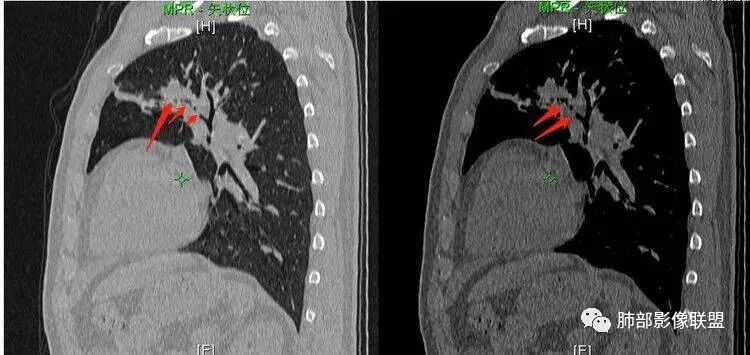

王秀仙:左肺上叶肿块,边缘平直收缩,周围可见长索条,轻度强化,密度不均可见低密度坏死,考虑结核。鉴别腺癌。Yiren  Sishui(厶水伊人):晨读:左肺上叶肿块,近胸膜侧光滑,提示符合淋巴回流病变,周围条索,符合肉芽肿性病变,环形强化,中心坏死,考虑结核可能luys:左肺上叶病变,沿支气管分布,边缘平直收缩,周围见长索条,轻度强化,伴边界可见低密度坏死灶。考虑特殊感染。灶内支气管中断,临床以咯血就诊,鉴别肿瘤。博麟:左上胸廓稍缩小,长条索病灶,冠状位似见支气管截断,坏死边界似乎欠清,猜个纤维条索基础上合并瘢痕癌红日东升:晨读:左上叶结块,前缘有粗大索条向前延伸,邻近前联合线明显左移,提示收缩明显。结块边缘平直、收缩;增强结块及索条明显强化,内血管走行自然,坏死灶周围似见三层结构;考虑炎性病变。wonderful:肿块实性边缘光滑  考虑良性病变 合并咯血 。结核或曲霉玫:左肺上叶不规则形软组织密度肿块影,边界清晰,期内密度不均匀,可见坏死,病灶向前呈条索状延伸,矢状位病灶形态欠规整,似有血管中断,考虑恶性病变可能,待除外结核?张帅:左肺上叶病变,病变周围平直,长毛刺,病灶内可见低密度区及支气管征,矢状位提示前段阻塞,病灶内气管不规则扩张,病灶周围有卫星灶,考虑良性病变:结核?我心飞翔:病灶边缘平直,中央可见坏死,周围磨玻璃边界欠清,考虑炎性病变张延军:左肺上叶尖后段肿块,边缘以平直为主,局部膨隆,内见片状坏死区,边界欠清,相应尖后段支气管闭塞,考虑占位并不张,腺癌?建议抗炎治疗后复查丽:左肺上叶病变,边缘平直,并可见长索条,增强后密度不均,可见坏死,首先考虑结核,但重建后支气管走形欠连续,似有截断,恶性待排毛勤香:左肺上叶病灶,边缘平直为主,周围索片影,增强强化不均匀,内有坏死,重建支气管走行欠规则,似有截断,老年男性,需排除恶性(鳞癌?)并阻塞性肺炎可能王萍:左肺上叶团片,大部分边缘平直、凹陷,周围见少许条片模糊影,增强内见坏死区,余区域较均质,其内支气管部分通畅,部分变窄。咯血病史,无发热,考虑肉芽肿性炎可能性大,结核或放线菌等,肿瘤待排THINKER:左上叶,占位,围绕尖后段支气管,U型凹丶平直,长索条,有轻强化及低密度,考虑良性的,首选OP,老年不发热丶咯血,鉴鳞癌、TB飞鹰行动:左肺病灶,有明显的收缩表现,增强后病灶内部可见低密度无强化区,病灶内支气管轻度扩张呈串珠状改变,支持炎性病变,结核可能性大。杨泽锋:支持炎性病变伴小脓腔形成,但不支持结核,因为病灶内可以可见血管影THINKER:问一下各位老师:这个给的强化,是肺动末期丶主动脉未期`延迟期?大雄:老年男性,左肺上叶前段条片状实变影伴周围长条索,境界清晰,边缘部分锐利光滑、部分毛糙,增强可见中央局部坏死,周围无强化区轻中度均匀强化,无钙化,无明显卫星灶,无胸膜明显牵拉凹陷。病灶整体收缩力有,张力不明显,肿瘤概率小。临床无明显急性感染症状,倾向于慢性增生性炎症,累及段支气管,引起了咯血。结核多见,但慢性结核肉芽肿一般强化没这么明显。OP不除外。老年男性如果有长期吸烟史,鳞癌不能完全排除,鳞癌的坏死强化都符合,鳞癌收缩力也不强,形态更是变化无常左手:老年男性,咯血,左肺上叶长条样结节,边缘见牵拉影,支气管堵塞,病灶内见坏死,坏死边缘偏清,考虑鳞癌,鉴别结核宇宙星空:支持恶性。鳞癌可能性大。支气管截断及空泡征

Shelia:考虑机化性肺炎伴小脓肿形成?炎性肌纤维母细胞瘤?鉴别癌食客:左肺上叶病灶,边缘平直,周围条片影,增强内见坏死区,内支气管部分通畅,咯血病史,无发热,考虑结核,肿瘤不除外。管洪林:左肺上叶尖后段病变,整体边缘平直,部分稍收缩,临近长索条影,胸膜缘可见轻度牵拉,增强后整体强化明显,其内可见低密度类圆形坏死区,边界清,首先考虑op并小脓肿形成,但部分层面显示小支气管受阻,是否层面原因?管洪林:若是支气管阻塞,鳞癌作为鉴别雪上一枝蒿(陈显静):他这个动脉期是不是不是很明显啊,觉得跟静脉期差不多,强化值也不好分辨?徐超:左肺上叶实变,边缘平直,周围无磨玻璃及卫星灶,病灶内坏死,强化后边界清楚,无壁结节,余病灶轻中度均匀强化(对比肌肉),增强后血管显影清楚自然,未见破坏边缘毛糙,血管旁条形无强化区(粘液?)整体符合炎性特点,炎性假瘤或op可能,伴小脓肿;结核放后面待排(结核病灶内血管完好,边缘清楚,且强化近中度,不是很合理,肉芽肿到也可以)。红日东升:平扫和强化窗宽窗位不一样良孑:左上实变,有平直及长毛刺,其内支气管牵拉性扩张,提示收缩力较强,无卫星灶,强化不支持TB,均匀强化,无分叶不支持鳞癌,影像上提示慢性进程,考虑OP并脓肿,鉴别炎肌母。

南边:应该是前段吧。前段的支气管怎么样?

宇宙星空:看远端的话是狭窄了吧,但是近端明显是截断啊,远端的是肺泡腔?

南边:坏死如何?

宇宙星空:是坏死吧,内壁边界不清

张延军:坏死边界清

宇宙星空:坏死明显

南边:还是支持炎性吧